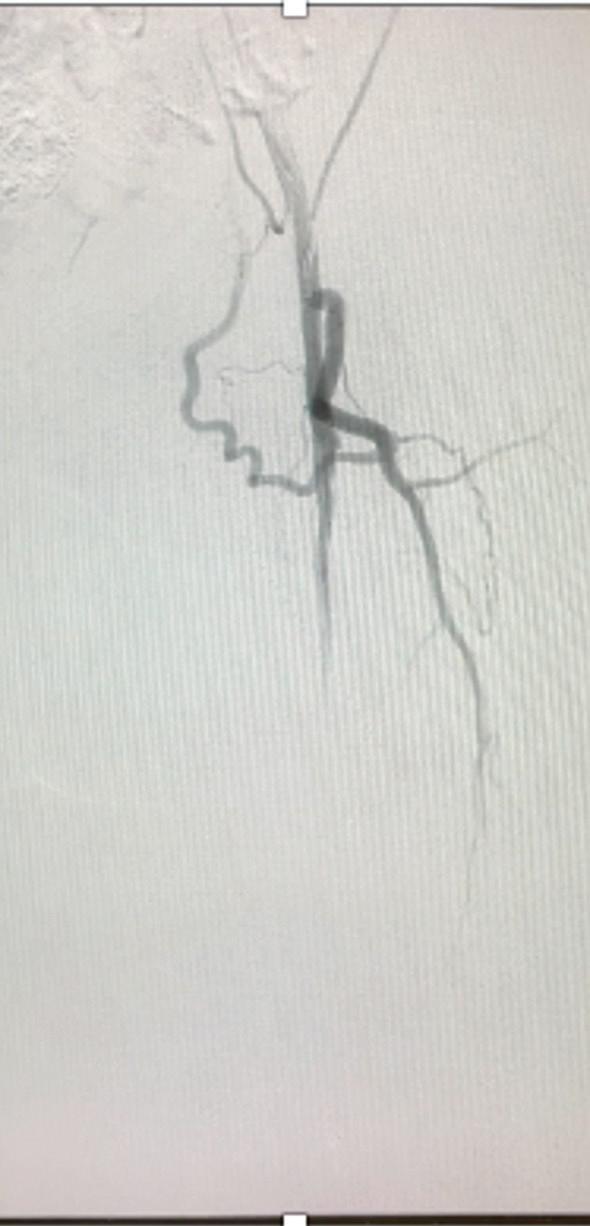

Post-intervention arteriogram

An excellent technical result was achieved. The SFA was widely patent with no significant residual stenosis. The posterior tibial and peroneal arteries were widely patent with brisk flow and no residual stenosis. Significantly improved flow was identified to the foot (Figure 4).